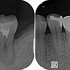

治療2回目 2個あったフィステルも無くなっていたので根管充填+レジンコアまで

2025 EEdental KOE (2).jpg

根管充填材はガッタパーチャー使用